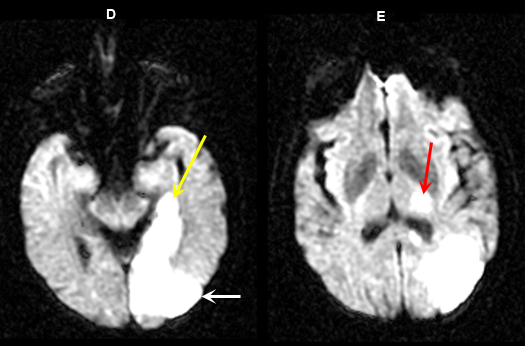

Figure 5 D-E: MR Images

Imaging findings: Figure 5 D-E (DW images)

Acute infarction involving the left occipital lobe (yellow arrow in Fig. A), adjacent left temporal lobe (white arrow in Fig. D) and infarction within the left thalamus (red arrow in Fig. E) is best appreciated on diffusion wtd. pulse sequences. |